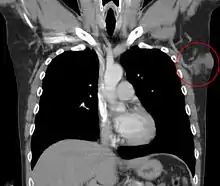

غالبا في كثير من الحالات يتم التشخيص الخاطئ للمرض على انه كيس دهن أو ما شابه وعلى انه ورم حميد وذلك التشخيص الخاطئ يجعل المريض يتجاهل الورم لسنوات عديده مما يزيد من حجم الورم. يمكن عن طريق التصوير بالرنين المغناطيسى (MRI) الكشف عن وجود الأورام، وللتأكد من التشخيص يمكن أخذ عينة من الورم عن طريق إبرة أو شق جراحي وفحصها تحت الميكروسكوب.[4]

غزو الورم للنسيج تحت الجلد على هيئة خلية نحل

البنية الضفيرية للورم

يتكون الورم من خلايا ليفية يافعة ومنسجات.

ترسب الهيموسيديرين أسفل الورم

صبغة مناعية إيجابية لCD34